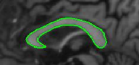

When the object is sparsely surrounded by competing regions, we observed that the segmented output is not critically dependent on the width of the annular region. The energy functional is well behaved without local minima affecting its performance. Figure 18 illustrates a case where the left ventricle in a MR scan of the brain is segmented with templates differing in their annular widths. An inner template is chosen and the width of the annular region is changed to generate these four templates. The right ventricle has same intensity profile as that of the left ventricle. This causes the right ventricle to become a potentially competing region, but the results indicate identical segmentation outputs despite the outer contour overlapping with the right ventricle to varying degrees in Figures 18(a), (b), (c), and (d) respectively. The experiment is repeated with multiple initializations and the consistency in final output is observed.

Refer to captionRefer to captionRefer to captionRefer to caption(a)(b)(c)(d)Refer to captionRefer to captionRefer to captionRefer to caption𝑎𝑏𝑐𝑑\begin{array}[]{cccc}\includegraphics[width=108.405pt]{15.pdf}&\includegraphics[width=108.405pt]{25.pdf}&\includegraphics[width=108.405pt]{35.pdf}&\includegraphics[width=108.405pt]{45.pdf}\\ (a)&(b)&(c)&(d)\end{array}

Figure 18: (a), (b), (c), and (d) are the converged results using various templates that share the same contour for the inner template and differ only in their outer template. The annular widths of the template in (a), (b), (c), and (d) are 15, 25, 35 and 45 pixels, respectively. The MR scan is taken from [44].